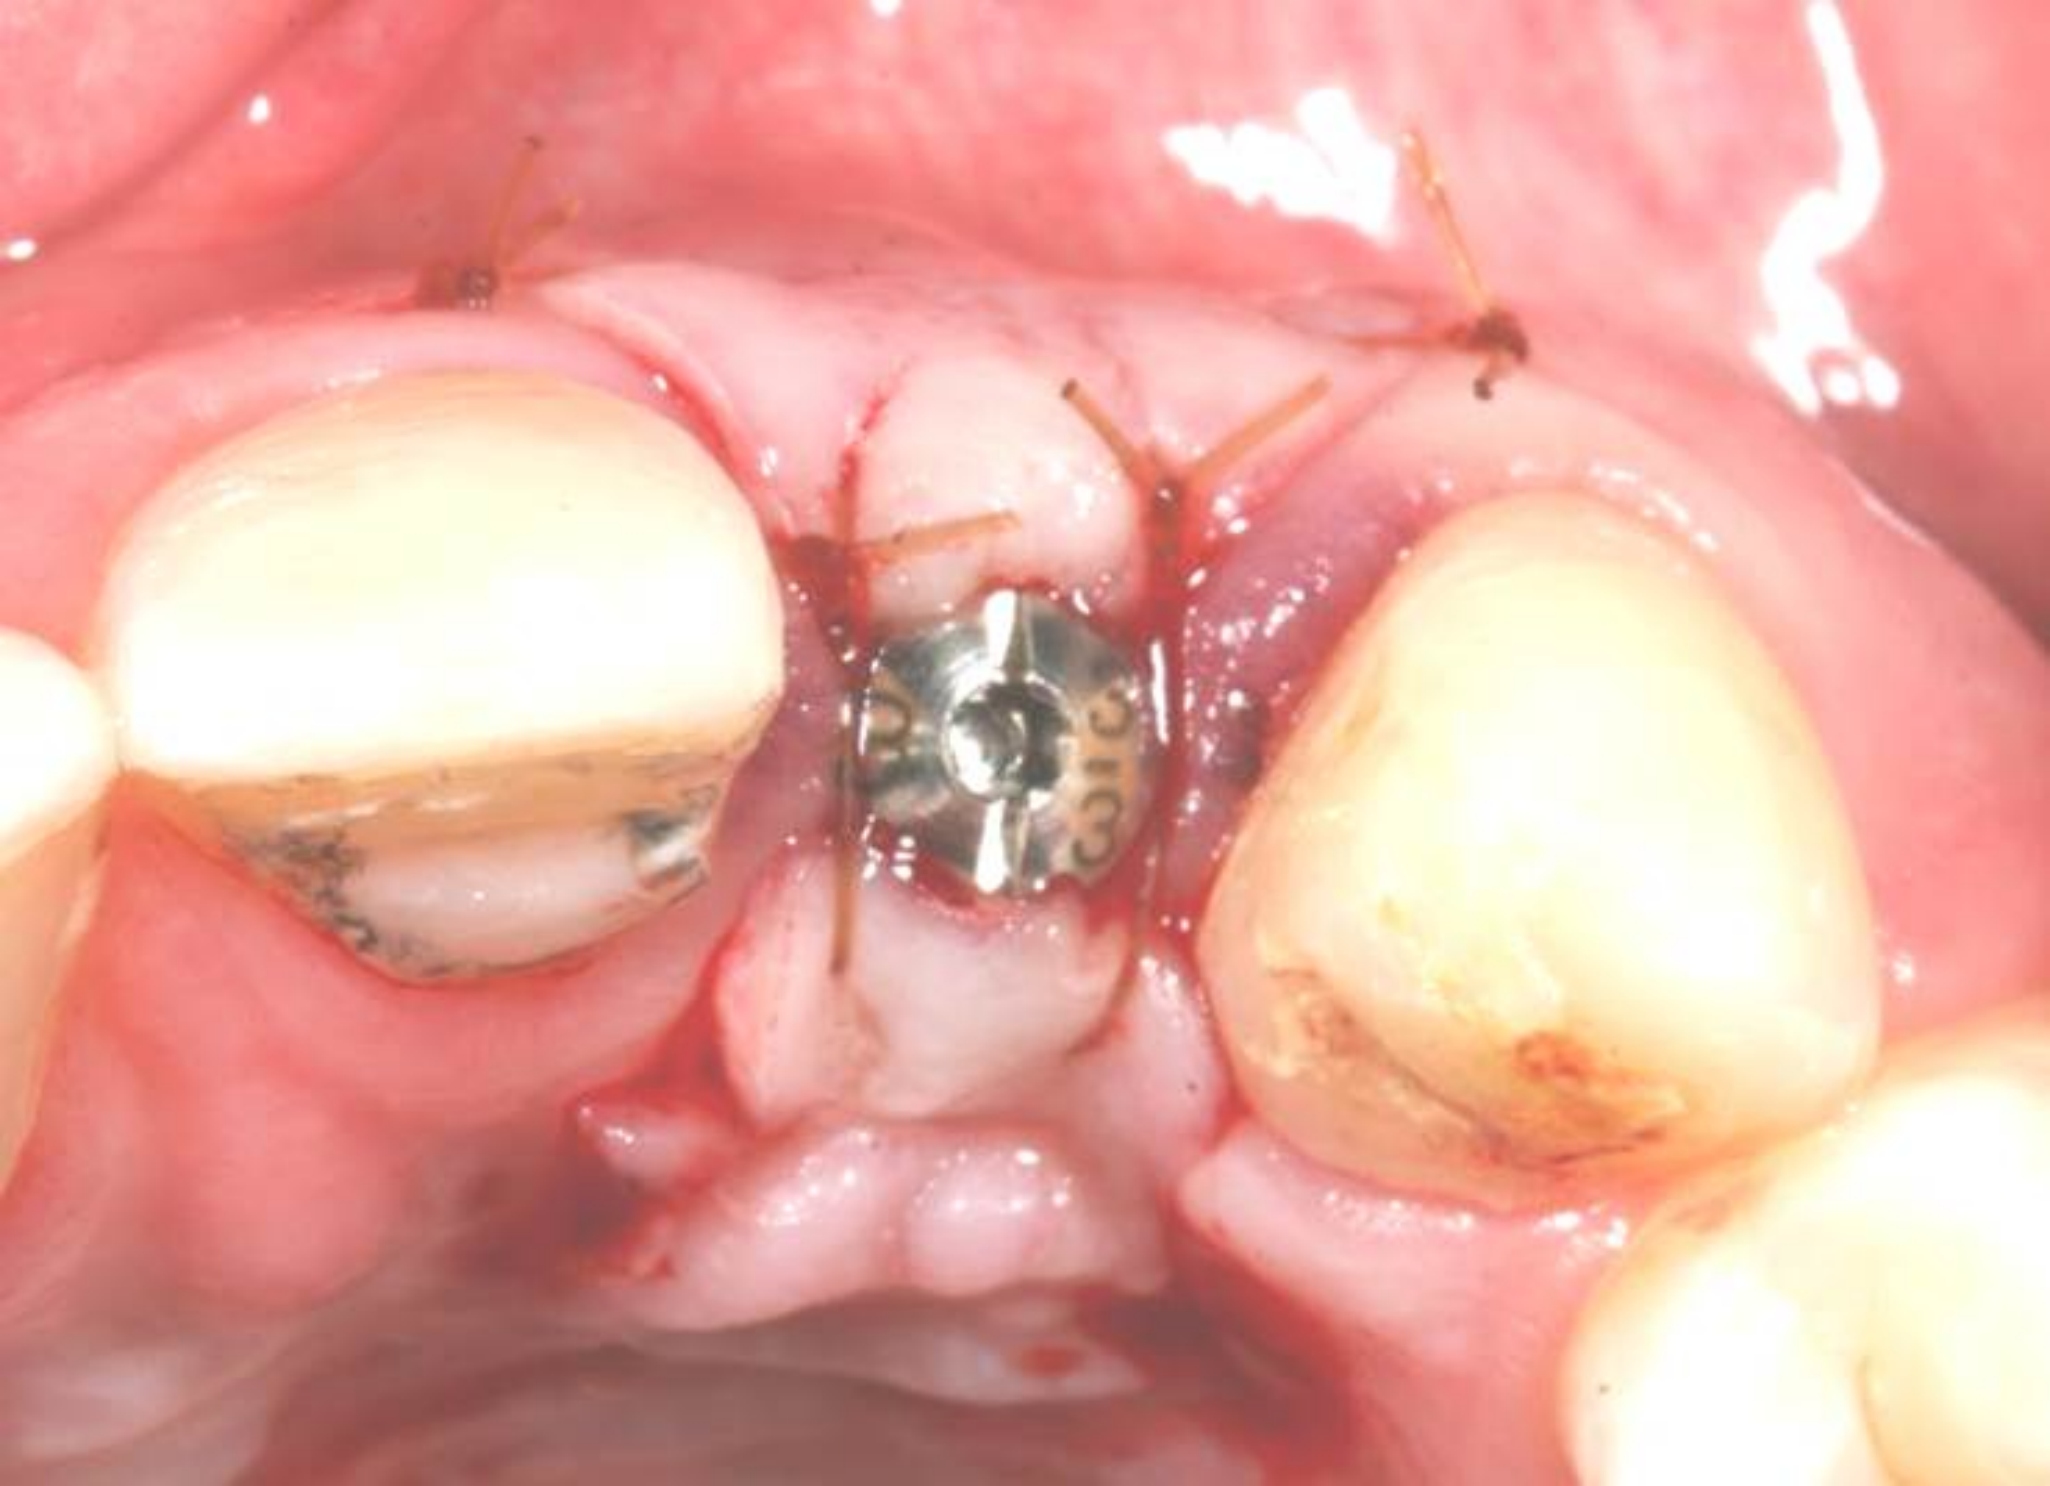

Case 3: Congenitally missing lateral incisors at the sites of teeth Nos. 7 and 10. Both sites were treated simultaneously. (Treatment at the site of tooth No. 10 is illustrated.)

Figure 19

Fig 20. Papillae-sparing incisions were developed both horizontally and vertically. The pedicle flap was elevated, exposing a thin ridge.

Figure 20